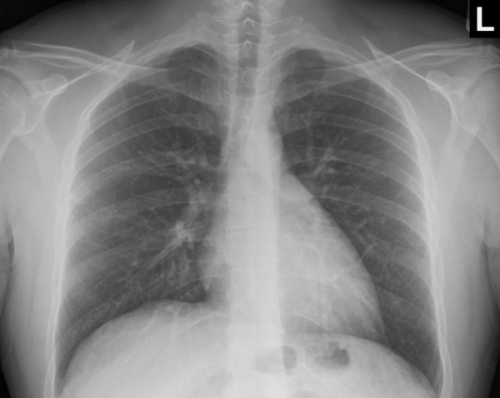

Tool to train medical student's eyes as to what a normal chest x-ray looks like, with over 500 consecutive normal images.